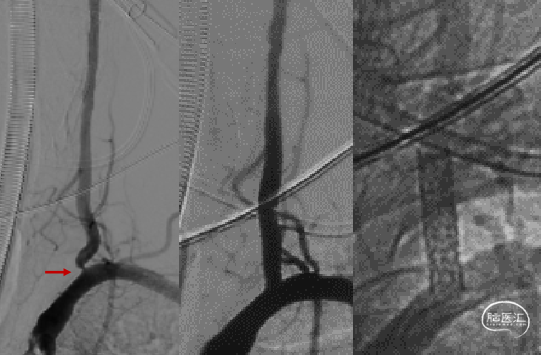

裸球扩支架

L-VA外周裸球扩支架植入;术后9个月复查,支架断裂;

支架内再植入一枚药涂球扩支架。